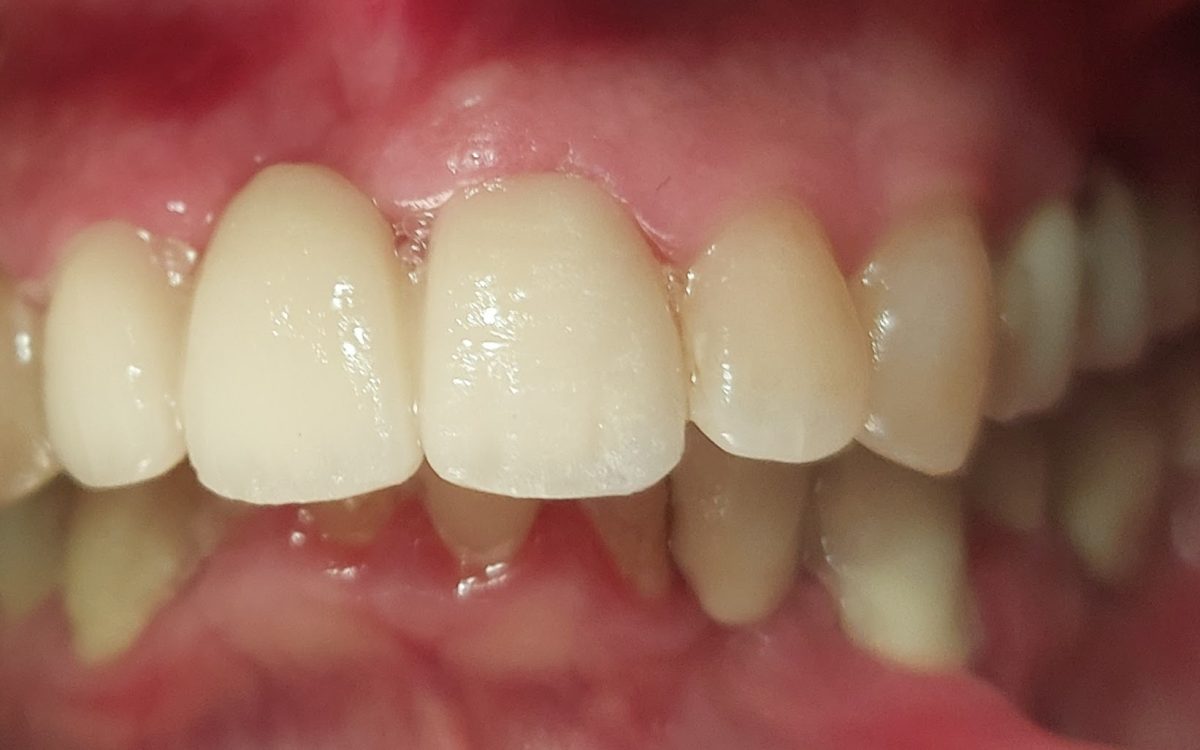

Fogászati korona

Hiányzó, sérült, vagy szuvasodott fogak pótlásának, helyreállításának egyik hagyományos és igen elterjedt eszköze a fogkorona.

Teljes porcelán, préskerámia korona

Fémmentes fogpótlás, cirkon korona

Porcelán (fémkerámia) fogkorona

Fémkerámia korona előnyei:

- Kedvező ár/érték arány: a fémkerámiából készült fogpótlás a legkevésbé terheli meg a pénztárcát, és jó alternatíva a régi, alászuvasodott koronák vagy híd cseréjére.

- Esztétikus: ma már a fémkerámia fogpótlás színe is lehet olyan, mint a meglévő fogaké.

- Modern technológiával történik az előkészítés: a régi fémkerámia koronák egy idő után elkezdték irritálni az ínyt, ami begyulladt és a korona és a fogíny találkozásánál szürke ínyszél alakult ki. Ma már vállas előkészítést alkalmazunk, aminek a lényege, hogy az íny helyett a fogra támaszkodik a korona, így elkerüljük az évek múlva kialakuló csúnya hatást.

- Tartós, stabil, strapabíró: A fémkerámia pótlásnak a váza fém, a felszíne kerámia. A fémvázat évtizedek óta alkalmazzuk a fogorvoslásban, jó technológiával készítve sokáig biztonsággal haraphat elkészült koronáin.

A cirkon korona előnyei:

- Anyaga: cirkónium-dioxid, melynek nagyobb a fényáteresztő képessége a fémkerámia fogpótlásokhoz képest. Ez az anyag olyan erős vázat képez, mely miatt fogorvosi hidak készítésére is alkalmas.

- Nem tartalmaz fémet, emiatt fémallergiásoknak is ajánljuk.

- Tartós, stabil, strapabíró: a fémkerámia pótlásokkal vetekszenek mechanikai tulajdonságai

Préskerámia korona:

- A préskerámia korona kiemelkedő esztétikájával tökéletesen illeszkedik a saját fogak közé, róla még közelről nézve sem mondható el, hogy fogpótlással állunk szemben!

- Elsősorban frontfogak (metszőfogak) helyreállítására alkalmazzuk, akár gyökérkezelt fogak esetén is. Mivel a préskerámia korona váza is fogszínű, ezért erősen elszíneződött gyökérkezelt fog esetén elsőként belső fogfehérítést kell végeznünk.

- Elsősorban szólókoronát készítünk belőle, híd készítéséhez inkább a cirkonkoronát javasoljuk.

- fémmentes, ezért fémallergiásoknak is javasoljuk

- anyaga préselt porcelán, mely tartós, akár kemény ételeket (répa, dió) is bátran lehet vele harapni

- előkészítéséhez minimális foganyag veszteséggel kell csak számolni (1 mm)